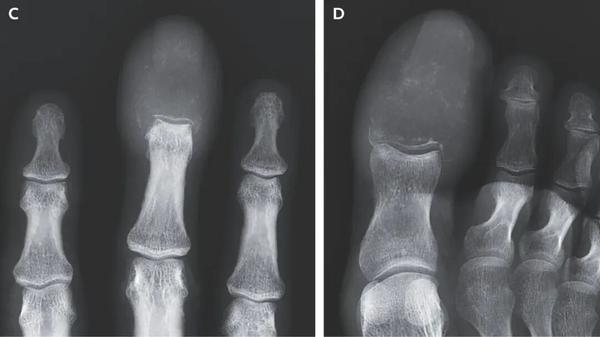

7月16日,《新英格兰医学杂志》(NEJM)发表了一份这样的病例报告:一名55岁的患者在6周内右手的中指和大脚趾接连出现疼痛和肿胀,指甲附近还长出了溃疡。

肿胀部位的触感十分坚硬,且有压痛感。虽然很像是痛风和骨髓炎,但患者的X射线扫描图给出了糟糕的结果——他的右手中指和大脚趾的骨骼几乎不见了。这是一种严重的溶骨性病变,一般由肿瘤引起。如果检测的结果是,骨骼中出现了破坏性的孔洞和大范围的阴影区域,不要意外,这也是溶骨性病变。

不幸的预兆

而NEJM论文中的患者有此遭遇,主要是出现了肿瘤转移。此前,他曾确诊了转移性鳞状细胞肺癌(metastatic squamous-cell lung cancer)。鳞状细胞是肺部气管内皮上的细胞,它们在受到长期刺激,比如吸烟后,就会发生癌变。而“转移性”指的是肿瘤从初始部位扩散到了新的地方,进入了发展晚期。目前这类癌症极难治疗,一直是科学家长期攻坚的方向。

虽然肺癌十分容易转移到骨骼,但转移到手指和脚趾的情况相对少见,仅占骨转移的0.1%。相比于靠近心脏的骨骼,比如脊柱、肋骨和骨盆,肢端的供血和骨髓含量明显更少,并不利于癌症生存,因此癌症扩散到肢端的案例很少。